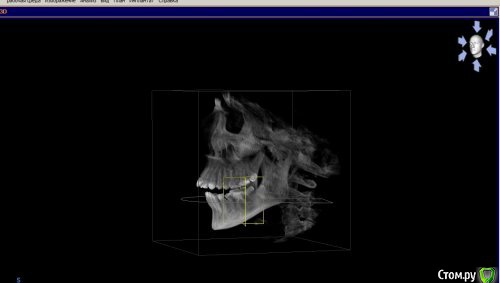

Ксения_занятый логин Опубликовано 29 марта, 2017 Автор Поделиться Опубликовано 29 марта, 2017 Прилагаю рентген Ссылка на комментарий

Brigita Опубликовано 31 марта, 2017 Поделиться Опубликовано 31 марта, 2017 по поводу Гербста - он выдвигает нижнюю челюсть вперед, в 27 лет сустав уже сформирован, на ОПТГ видно, что при выдвижении челюсти для закусок она находится в максимально переднем положении, особенно справа. Для того, чтобы определить не пострадает ли сустав от таких перемещиений - нужно сделать снимок в конструктивном прикусе, изготовить такой силиконовый сплинт, на расстояние, которое ортодонт хочет переместит челюсть и с ним уже на снимок. Посмотреть на сустав. Убедится в ложности такой идеи.Вы, возможно добьетесь какого то результата со стороны зубов, они у вас сомкнутся наконец, но заработаете очередную проблему - сустав. Ссылка на комментарий